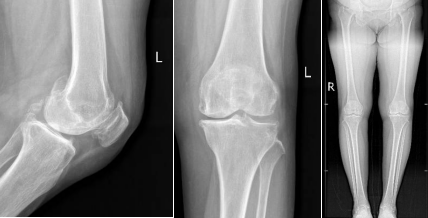

患者術(shù)前DR